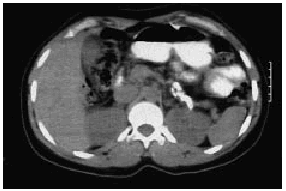

En las determinaciones analíticas practicadas destacaban: amilasas 350 U/l, y leucocitos, 14.000/ml, siendo el resto de la analítica habitual normal. Se realizó un test de sobrecarga oral de glucosa, que fue normal. Las cifras de magnesio sérico fueron 1,8 mg/dl (valores normales [vn], 1,8-2,9 mg/dl) y de selenio 76 ng/l (vn, 46-143). En la radiografía simple de abdomen se objetivaron calcificaciones en el hipocondrio izquierdo (figs. 1 y 2). En la ecografía abdominal se observaba una ectasia ductal pancreática y la presencia de calcificaciones grandes e irregulares localizadas en el cuerpo y en la cola del páncreas, siendo el resto de la exploración normal. Se realizó una tomografía axial computarizada (TAC) abdominal para completar el estudio, en la que se encontraron múltiples calcificaciones pancreáticas grandes localizadas de forma predominante en la cola pancreática, aunque alguna también en la cabeza, sin dilatación del conducto pancreático y con una disminución del volumen del parénquima pancreático respecto del que correspondería por su edad (fig. 3). También se realizó una gastroscopia sin alteraciones y un test de Van de Kamer, que fue normal.

Fig. 2.

A diferencia de la pancreatitis alcohólica, en que las calcificaciones suelen ser pequeñas, espiculadas, irregulares y mal delimitadas, la radiología de la pancreatitis crónica tropical suele evidenciar cálculos grandes (aunque variables en tamaño), bien delimitados y densos tanto en el conducto pancreático principal como en los conductos secundarios. Se suele observar también dilatación del sistema canalicular. La radiografía es de gran ayuda en el diagnóstico y, de hecho, en los países de alta incidencia constituye, junto a la clínica, el principal recurso diagnóstico20.